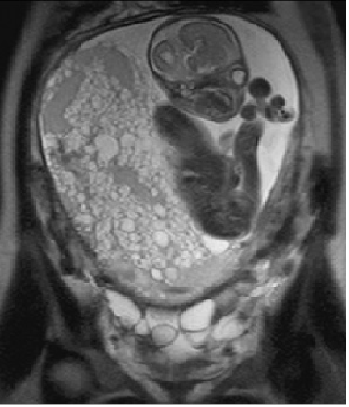

В редких случаях бывает и так: Двойня: полный ПЗ и жизнеспособный плод (МРТ) http://www.clinicaloncology.com.ua/article/6297/monitoring-bolnyx-posle-udaleniya-puzyrnogo-zanosa